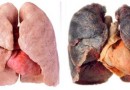

폐암

폐암 (정상 폐) (폐암)(정의)폐암이란 폐에서 비정상적인 암 세포가 무절제하게 증식하여 종괴(덩어리)를 형성하고 인체에 해를 미칠 때 이를 폐암이라 합니다. 폐 내에 국한되어 발견되기도 하지만 진행되면 반대쪽…

만성 폐쇄성 폐질환

만성 폐쇄설 폐질환 (정의)만성폐쇄성폐질환은 나이가 들면서 생기고, 오랜 기간 동안 담배를 피운 사람한테 잘 발생하는 병입니다. 약어 COPD는 '만성폐쇄성폐질환(Chronic Obstructive Pulmonary Disease)' 영문표기의 앞머리 글자만을 따온 …